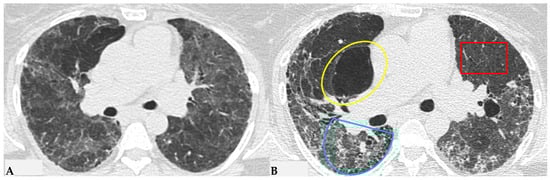

The fibrotic damage in HP is often more severe and extensive in the middle or middle-lower lung zones, but at times, it can be equally distributed across all three lung zones with relative sparing of the subpleural compartment, presenting a “patchy” distribution as a trace of a previous inhalation-mediated immune attack. This distribution may not always exhibit a clear central or peripheral predominance, as evident in axial assessments or MPR reconstructions [7,8,9]. The obstruction of small airways, another significant and distinctive feature of HP, can manifest with various characteristics. In (NFHP), poorly defined centrilobular nodules (fluffy nodules) and mosaic attenuation can be observed. The corresponding HRCT semiotics in FHP presents a “three-density pattern” (Figure 5), characterized by the simultaneous presence of pulmonary lobules with normal density, lobules with (GGO) and lobules with reduced density and size of vascular structures (mosaic attenuation/air trapping) due to air entrapment resulting from broncho-obstruction (Figure 6). The three-density pattern becomes more evident in expiratory HRCT scans due to the air entrapment resulting from the pathogenesis of bronchiole obstruction [4,10].

Figure 5.

FHP: chest HRCT ((A,B): axial scan). Visible is the “three density pattern”, with areas of the lung with normal density spared from pathological changes (red box); areas of the lung with reduced density characterized by a paucity of vascular and bronchial structures (yellow box); areas of the lung with increased density showing reticulations, interstitial thickening and traction bronchiectasis (green box). Lung cyst (red arrow) and areas of smoking-related paraseptal emphysema and advanced destructive emphysema (ADE) (blue arrows) are also present.